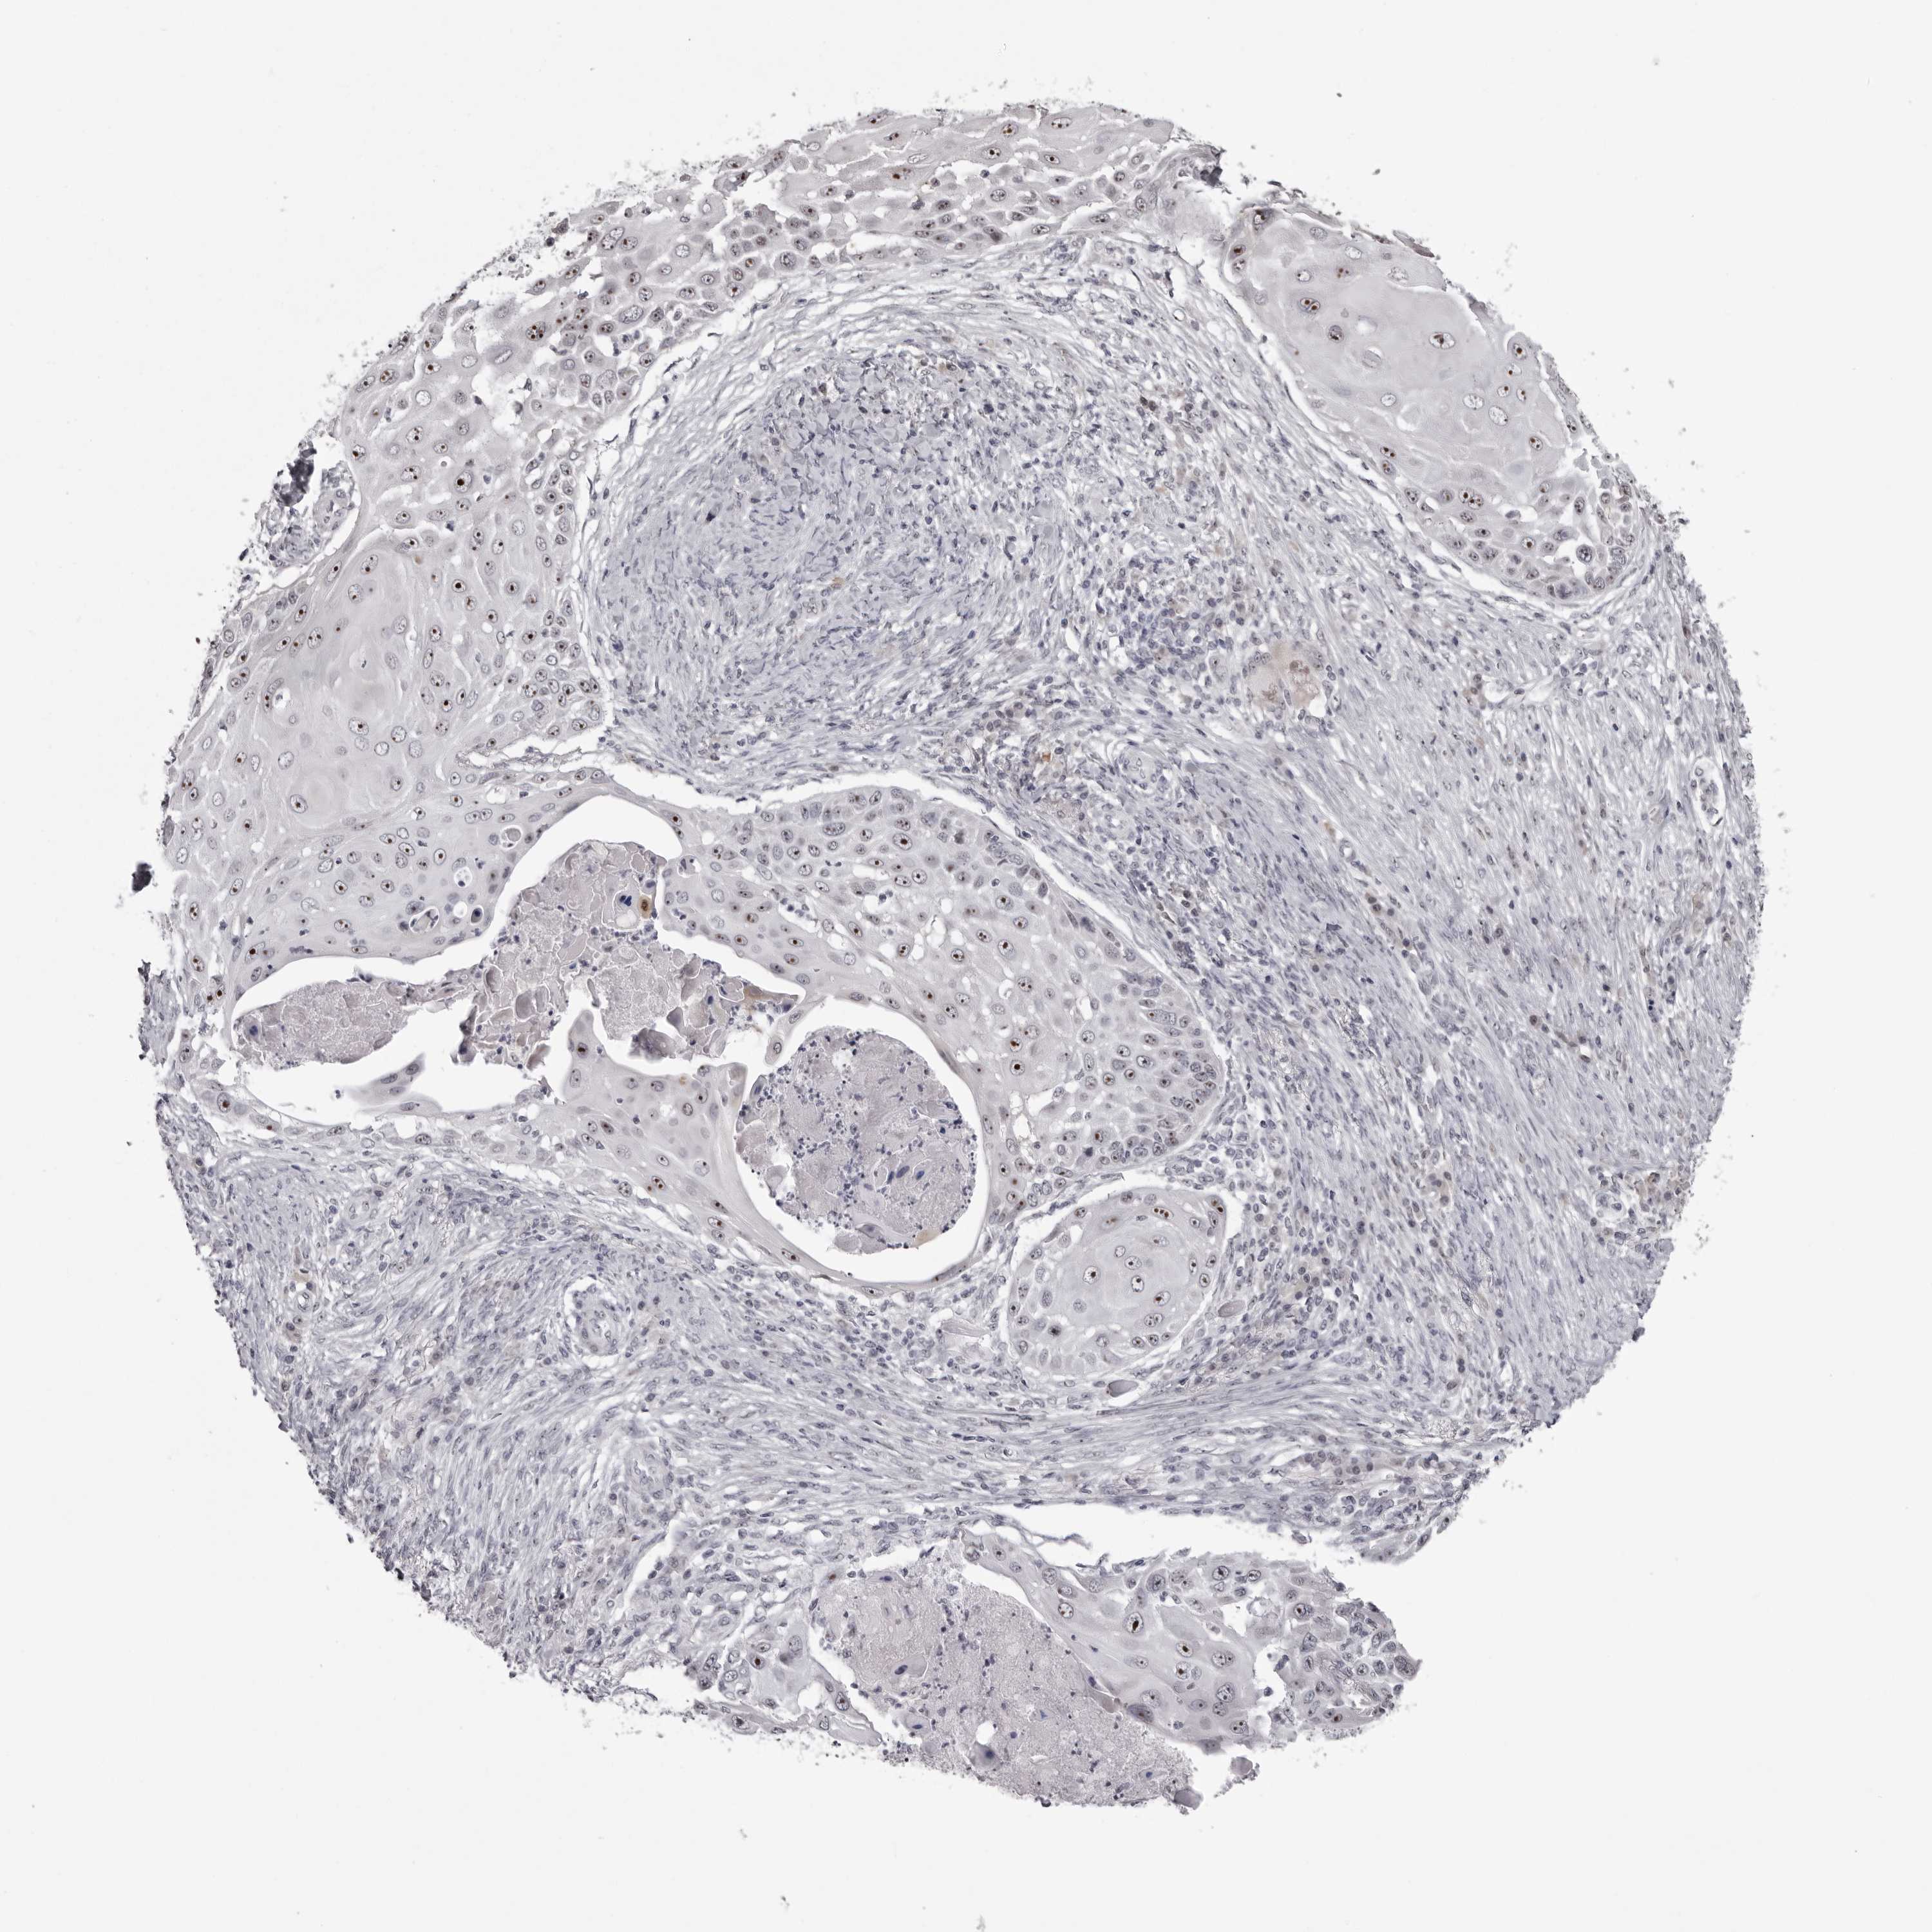

CANCER SKIN CANCER Show tissue menu

Basal cell and squamous cell cancer

SKIN CANCER - Protein expressioni

A mouse-over function shows sample information and annotation data. Click on an image to view it in a full screen mode. Samples can be filtered based on level of antibody staining by selecting one or several of the following categories: high, medium, low and not detected. The assay and annotation is described here.

Each image is clickable and will lead to virtual microscopy that enables deeper exploration of all samples and also displays staining intensity scores, fraction scores and subcellular localization as well as patient and tissue information for each sample.

Antibody HPA028276

Basal cell carcinoma